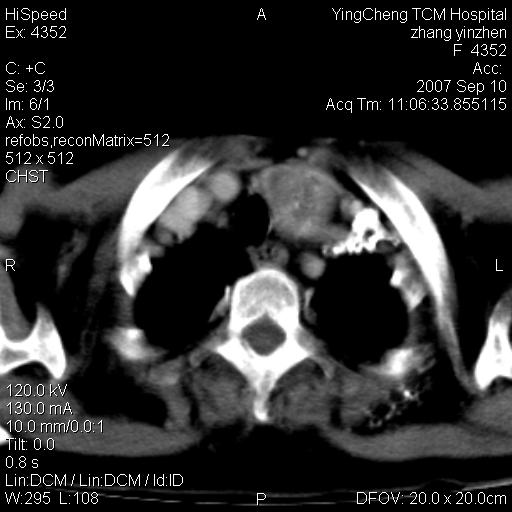

以下是引用卜一在2007-9-18 14:41:00的发言:[br]右肺肿块:毛刺+胸膜凹陷征+供血血管+浅分叶+强化。支持:周围性肺癌 !另:左侧甲状腺腺瘤!

以下是引用夏季在2007-9-18 11:00:00的发言:[br]1。右肺肿块,周围有短毛刺,肺门侧有血管与其相连,胸壁侧有胸膜凹陷征,考虑周围性肺癌 2。左侧甲状腺软组织肿块,内有高密度钙化灶,考虑左侧甲状腺腺瘤。